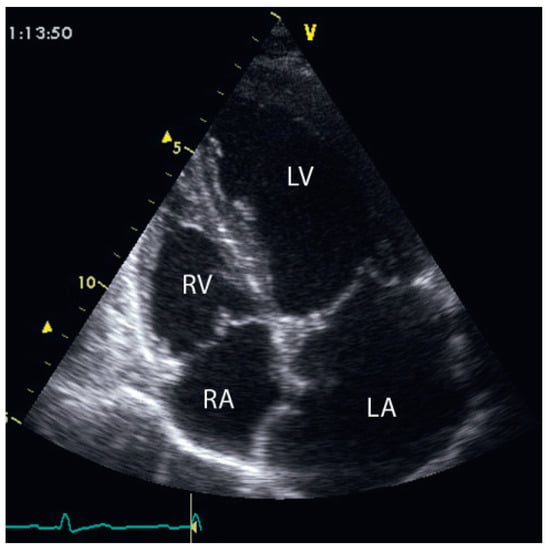

Up to ten percent of acute coronary syndromes occur during or shortly after physical exercise. In fact, physical exertion of more than 4 METs transiently increases the risk for myocardial infarction which remains elevated until an hour afterwards. Th...